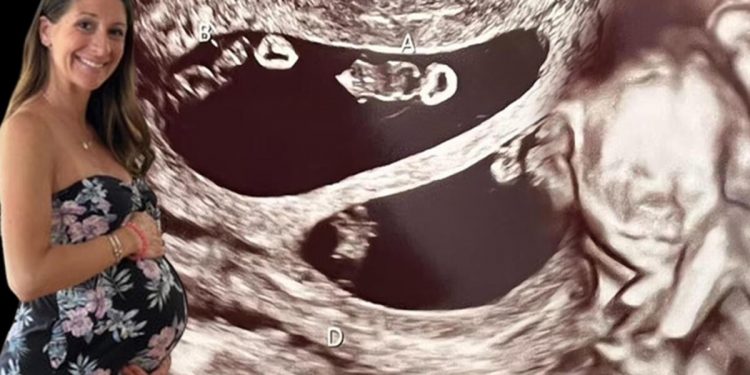

ABD’nin Massachusetts eyaletinde yer alan Taunton’dan kuaför olan 35 yaşındaki Ashley Ness, Şubat ayında rutin denetimleri için gittiği hekiminden gebe olduğu haberini aldığında dünyalar onun onun oldu.

Ashley, 2 hafta sonra 47 yaşındaki erkek arkadaşı Val ile birlikte ultrason denetimine gittiğinde sevinci büyük şoka dönüştü ve bir değil tam dört bebeğe gebe olduğunu öğrendi.

Daha evvelki bağından de bir kızı olan anne adayı karnındaki dört bebeğin dördüz değil iki farklı tek yumurta ikizi olduğunu öğrendi.

Bu keşfin ultrason teknisyenini bile şoke ettiğini anlatan anne adayı, “Taramayı birinci başlattığı vakit ekrana baktı ve ‘A,B’ yazdı. Durup bir an ona baktım. Görünen o ki ikizlerim olacaktı.” diye kelamlarına başladı ve şöyle devam etti;

“Teknisyenin başının karıştığını görebiliyordum. Ekranda gördüğü şeyin gerçek olup olmadığını anlamak için odadan çıkmak zorunda kaldı. Döndüğünde ise bana inanılmaz durumu anlattı. Dört bebeğe hamileydim. İki kız ve iki erkek.”

70 MİLYONDA BİR GERÇEKLEŞİYOR

Haberi birinci duyduğunda ve tabipler bunun 70 milyonda bir gerçekleştiğini söyleyince bayılacak noktaya geldiğini anlatan Ashley, “Tarama devam ediyordu lakin ben olayı anlamaya çalışıyordum. Erkek arkadaşıma 4 bebeğimiz olacağını nasıl söyleyecektim? Aileme nasıl söyleyecektim?” tabirlerini kullandı.